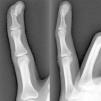

Mujer de 29 años, que consulta por tumefacción y dolor en el quinto dedo de la mano izquierda, de 3 meses de evolución. No presentaba antecedentes médicos de interés y no refería traumatismo previo en el dedo. A la exploración, presentaba una tumoración de 1,5×0,5cm en el pulpejo y la región subungueal, de consistencia indurada, adherida a planos profundos, con eritema leve y dolor a la palpación. El estudio radiológico mostraba una lesión nodular osificada, bien delimitada, de bordes irregulares, adherida al periostio de la falange distal del dedo afectado, sin erosión de la cortical (fig. 1). La analítica, incluyendo bioquímica, hemograma y reactantes de fase aguda, fue normal. Se realizó la exéresis de la lesión y el estudio histopatológico reveló que estaba constituida por tejido fibroso con fibroblastos con núcleos prominentes sin atipia en su periferia y depósitos de osteoide inmaduro rodeados por un ribete osteoblástico en su zona central (fig. 2). Dichos hallazgos fueron compatibles con el diagnóstico de periostitis reactiva florida de la mano (PRFM). No hubo recidivas de la lesión.

La PRFM es una entidad benigna rara caracterizada por una exuberante producción osteoblástica en un estroma fibroso proliferativo originada a nivel del periostio de los dedos1. Su patogenia es desconocida, pero se considera que corresponde más a un proceso reactivo que a una neoplasia, estando presente el antecedente traumático hasta en un 50% de los casos2. Aunque fue descrita en 19333, existe hasta la fecha importante confusión en la literatura debido a sus diferentes denominaciones, que incluyen fascitis paraostal, fascitis osificante, seudotumor fibro-óseo, tumor óseo seudomaligno de los tejidos blandos de los dedos y fascitis nodular, siendo PRFM la más aceptada2,4. Se localiza con mayor frecuencia en la falange proximal, seguida por la falange media, metacarpianos y falange distal, siendo rara en el primer dedo2. Ocurre generalmente en mujeres durante la segunda y tercera décadas de vida, y clínicamente se caracteriza por tumefacción, dolor y eritema del dedo afectado2,5. Las radiografías muestran aumento de partes blandas y neoformación ósea perióstica, que puede tener un aspecto lamelar o de hueso maduro5. La cortical generalmente está intacta, aunque se han descrito ocasionalmente erosiones6. El diagnóstico diferencial incluye infecciones (tenosinovitis séptica, absceso de partes blandas con alcance óseo, osteomielitis cortical), miositis osificante, tumores benignos como el de células gigantes de la vaina tendinosa y el osteocondroma, y malignos como el osteosarcoma paraostal y periostal, el sarcoma sinovial y el condrosarcoma periostal1,5. El tratamiento recomendado es la escisión local, que es curativa en la mayoría de los casos5. En conclusión, aunque la PRFM es una lesión infrecuente, conviene tenerla en cuenta debido a que puede simular otros procesos más graves, como las neoplasias óseas malignas.